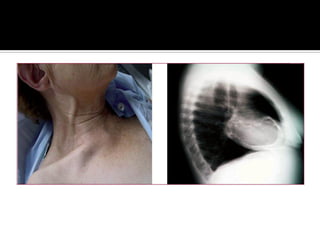

   El hallazgo semiológico más propio de la pericarditis constrictiva es

el signo de Kussmaul o aumento de la presión venosa yugular

(ingurgitación yugular) durante la inspiración, como

consecuencia de un aumento del retorno venoso, secundario a la

presión negativa intratorácica, pero con restricción al llene

ventricular derecho y sin que haya un aumento simultáneo del gasto

cardíaco. Dado que el corazón está recubierto por una coraza

rígida, la distensibilidad de este se ve muy disminuida y cualquier

aumento de volumen se transmite en forma retrógrada, es por eso

que las yugulares se ingurgitan al inspirar (no como normalmente se

esperaría: al inspirar, las yugulares colapsan)

   O… en valsalva.